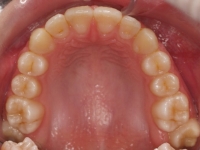

Paciente que acude a nuestra consulta para tratar el apiñamiento. Se realizó el tratamiento con férulas INVISALIGN con una duración de 12 meses.